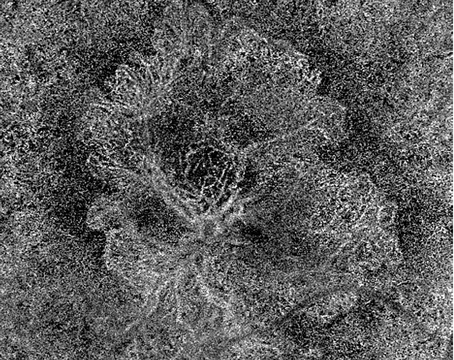

Retinal autograft with retinectomy and the SPOT technique for macular hole

The technique can be very useful in the setting of highly myopic PVR re-detachment.